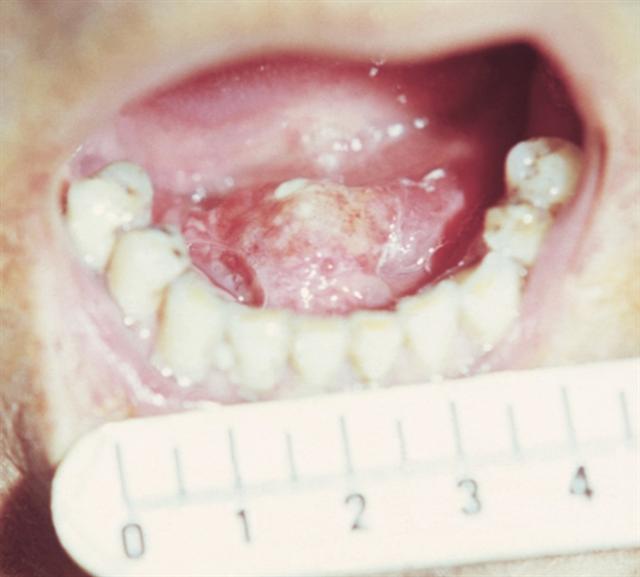

Рис. 5. Рак языка с переходом на дно полости рта.